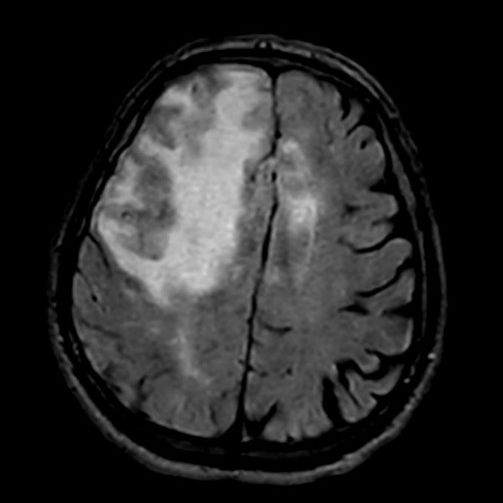

- A) Aksiyel planda FLAIR sekansta asimetrik kortiko-subkortikal vazojenik ödemi düşündüren yüksek sinyalli hafif ekspansil lezyonlar (turuncu ok).